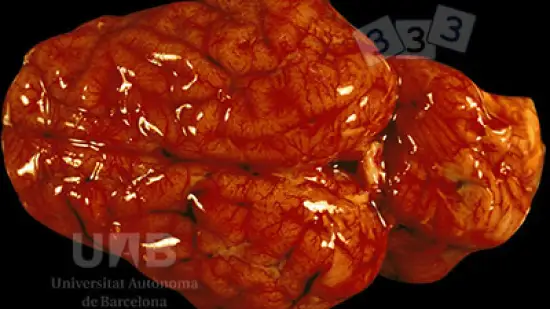

Les points rouges observés au centre des lobules hépatiques sont évocateurs de...